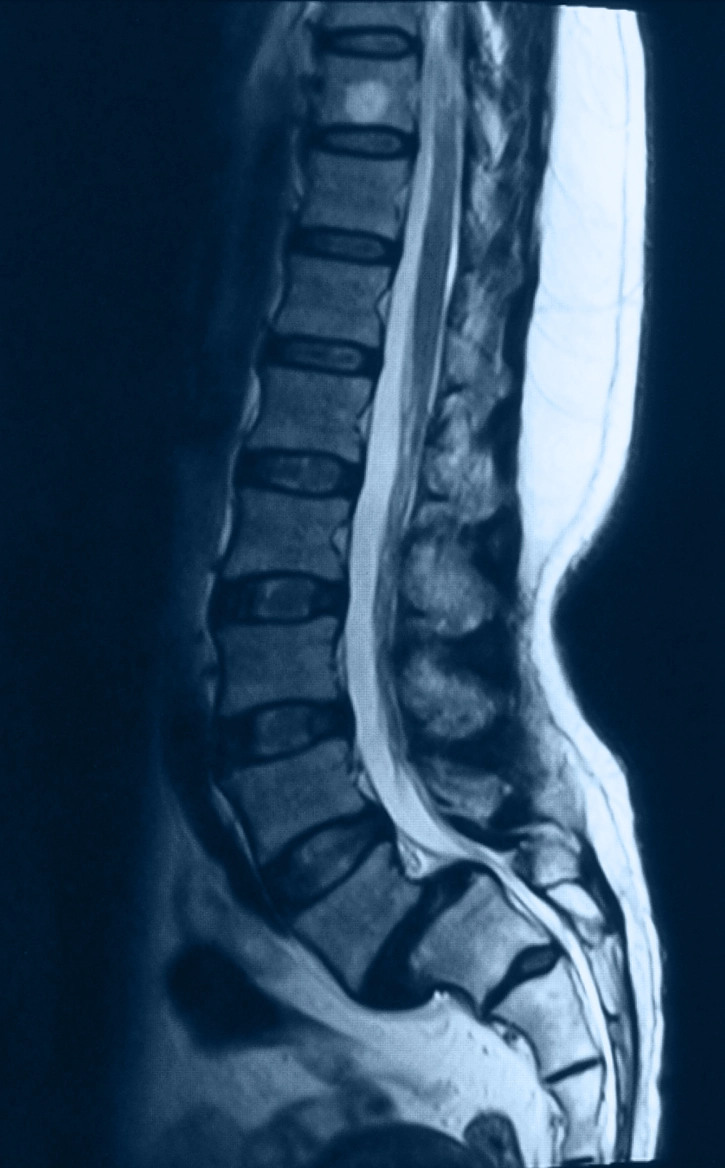

Spondylolisthesis occurs when one vertebra slips forward over the bone beneath it. This misalignment can create instability in the spine and place pressure on nearby nerves, leading to pain and reduced movement.

It most commonly affects the lower back (lumbar spine), and spondylolisthesis treatment can vary depending on whether the slippage is mild or more advanced.

- X-rays to assess vertebral alignment

- MRI or CT scans to evaluate nerve involvement

This allows Dr. Hodges to determine the degree of slippage and whether nerves are affected.